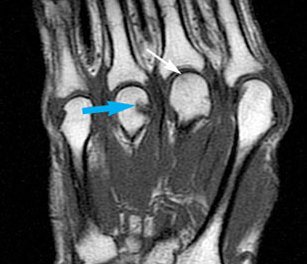

Images taken 7 months apart show subtle densities of the left knee that has been causing pain. The woman also has subluxation of the fingers, without erosion.